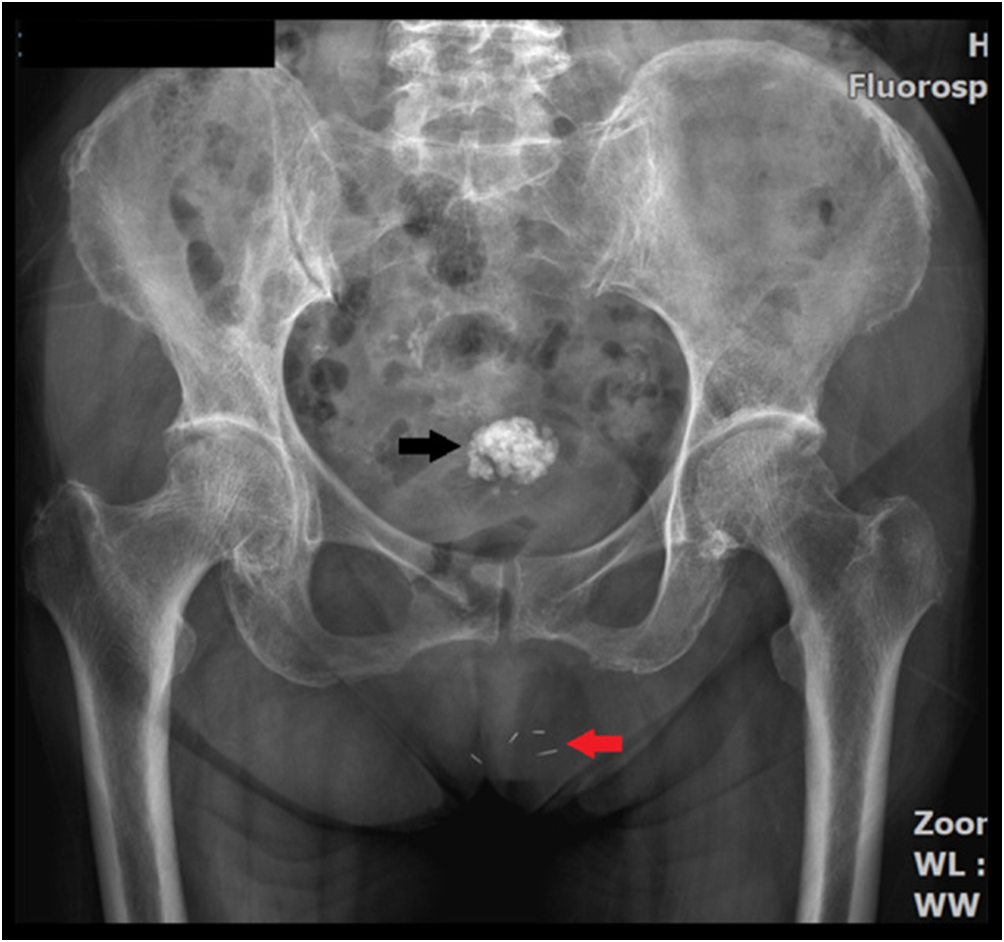

Внешне их никак не видно. и так как используются благородные металлы, вреда организму не бывает, амулеты можно увидеть только на рентгенограмме.

Полюбоваться, как это выглядит, вы можете на рентегнограммах